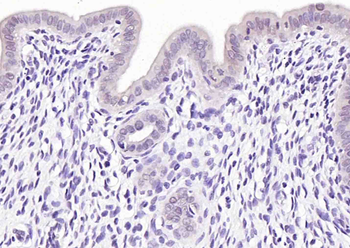

200 μl, 50 μl, 100 μlPhospho-CDKN1A/p21 (Thr57) Rabbit Polyclonal Antibody [orb6569]

FC, IF, IHC-Fr, IHC-P

Mouse, Rat

Human, Mouse, Rat

Rabbit

Polyclonal

Unconjugated

100 μl, 200 μl, 50 μl